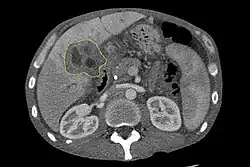

Sonographie und Computertomographie des Oberbauchs

Bei Hinweisen auf einen Verschlussikterus wird häufig als erstes bildgebendes Verfahren zur Darstellung der Gallenwege die Oberbauchsonographie eingesetzt.[40][41] Mit dieser Methode kann die Verlegung und Aufweitung der Gallengänge untersucht werden und in Einzelfällen kann auf diese Weise schon die Diagnose eines Gallengangskarzinoms gestellt werden.[42] Auch die Computertomographie spielt eine große Rolle bei der Untersuchung dieser Patienten.[43][44][45]